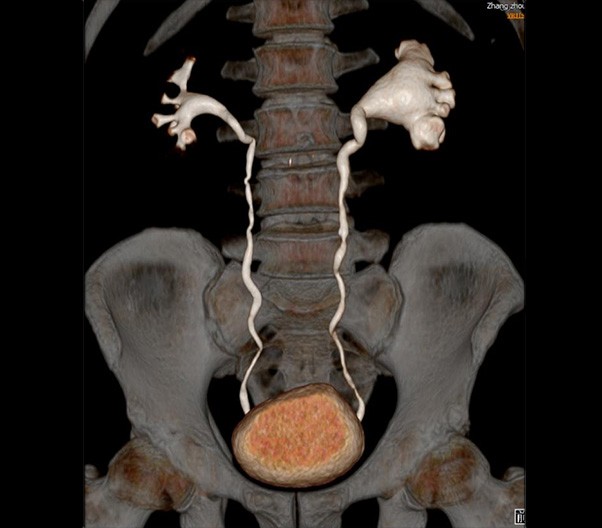

The 1024-pixel image matrix brings superior image clarity (0.6 mm slice thickness) and stimulates the early detection of small lesions, thus improving diagnostic reliance.

ScintCare CT 16 incorporates an entirely digital integrated ScintiStar detector, which was solely developed by MinFound, from material to the whole structure design, based on the technical know-how of our skilled scientific team. The system produces high-resolution images with a low radiation dose and an excellent signal-to-noise ratio.

NDI NanoDose Iteration Algorithm (NDI) is an innovative iterative technique for image reconstruction that takes full advantage of deep learning in anatomical structure in image space as well as model-driven iteration involving tube and detector in projection space, with the aim to generate sharp and high-resolution images at the lowest possible dose.